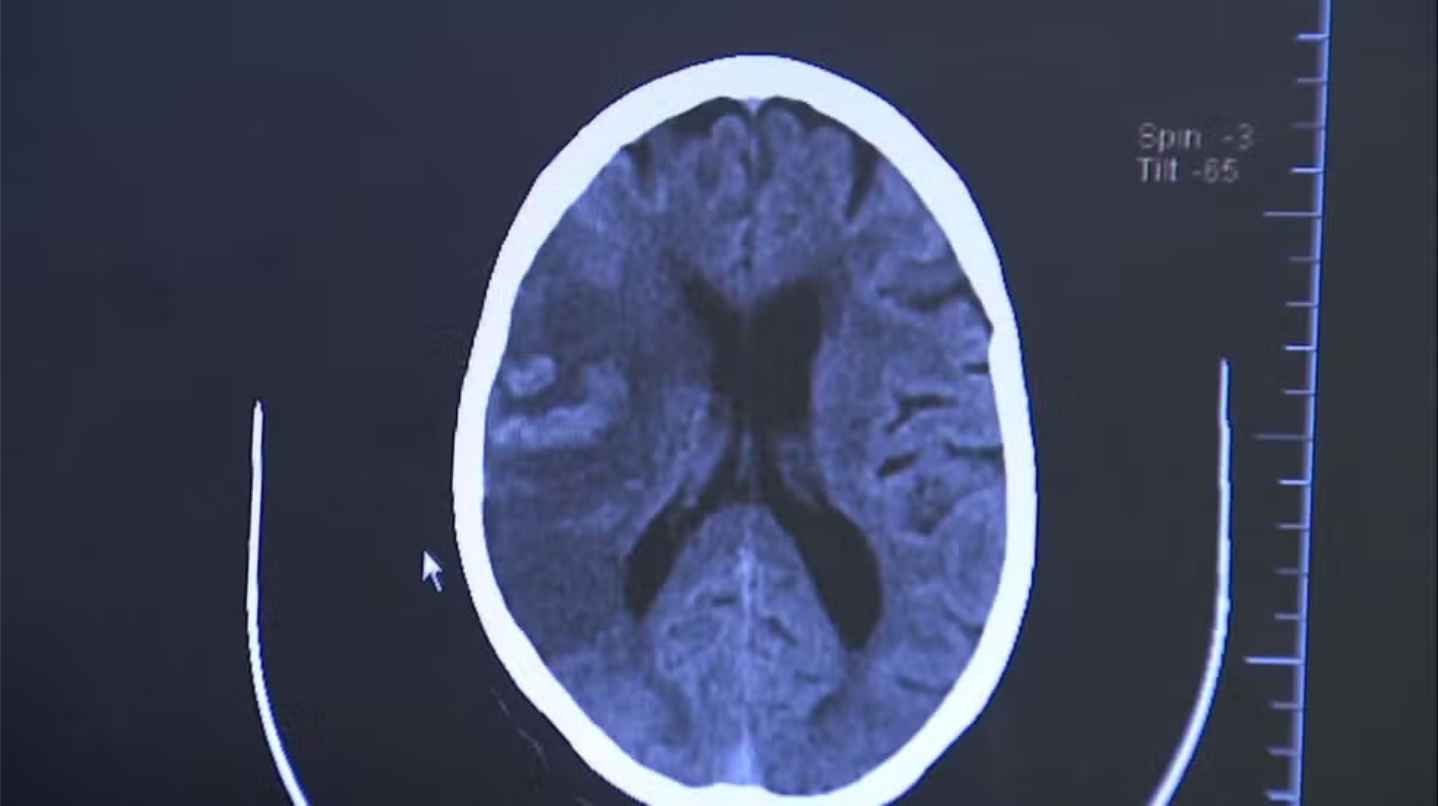

O acidente vascular cerebral (AVC) é uma das maiores urgências médicas do país — e uma das principais causas de morte entre os brasileiros. Ao lado do infarto, integra o grupo das doenças cardiovasculares, que respondem por cerca de 30% dos óbitos anuais, segundo o Ministério da Saúde. De janeiro a outubro deste ano, 64.471 pessoas morreram em decorrência do AVC, o equivalente a uma vida perdida a cada seis minutos. No ano passado, foram 85.457 mortes, segundo dados do Portal da Transparência dos Cartórios de Registro Civil, número que mantém o Brasil entre os países com maior carga da doença. O custo da doença também é alto. Entre 2019 e setembro de 2024, o tratamento de pacientes com AVC consumiu R$ 910 milhões do sistema hospitalar. Foram mais de 85 mil internações, e um em cada quatro pacientes precisou de leito de UTI. Segundo o Ministério da Saúde e a Sociedade Brasileira de AVC (SBAVC), oito em cada dez casos poderiam ser evitados. O segredo para evitar o problema está em controlar os principais fatores de risco, que são: hipertensão; diabetes; obesidade; tabagismo; sedentarismo; e colesterol alto. Foto: Durante o AVC isquêmico há um bloqueio na artéria, levando à falta de sangue e morte das células cerebrais. Já no hemorrágico, o sangue extravasa por ruptura de um vaso — (Fonte: G1 / Foto: Reprodução EPTV).